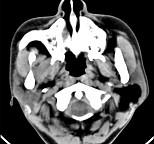

问题 男性38岁,左侧腮腺渐进性肿大1年,无压痛,CT扫描如图所示,请选择正确的描述和结论()

选项 A.左侧腮腺区见低密度肿块,CT值约为-200HU B.肿块边缘清楚,未见邻近结构受侵 C.考虑为囊肿 D.考虑为脂肪瘤 E.考虑为血管瘤

答案 ABD